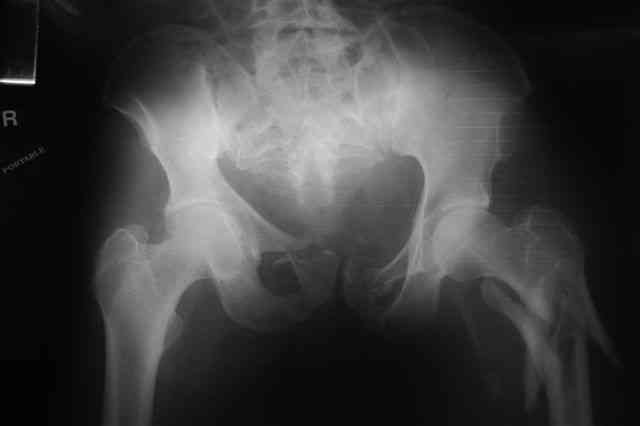

Я помню технику транссакральной фиксации тазового кольца длинными 5 мм Шанцами - повреждения типа В, в этом же случае задний отдел тоже вовлечен

т.е комбинированная нестабильность, поэтому вопрос - достаточно ли только двух Шанцев для стабилизации таза? Что вы думаете об anterior Right SI joint plating + tension band plating from the back.?

PS после фиксации бедра под Эопом посмотрел инлет и аутлет проекции, насколько репонируемо смещение правой половины таза *невооруженными*

руками - никаких шансов улучшить позицию иначе бы конечно воспользовался длинными Шанцами сразу после бедра.

По-поводу фиксации таза спонгиозными винтами. Данный способ все-таки показан для фиксации повреждения крестцово-подвздошного сочленения или переломов крестца. Мне кажется, что в данной случае ситуация иная - имеется перелом "основания" крыла подвздошной кости (в который вовлечена и поверхность, составляющая крестцово-подвздошное сочленение). Не уверен, что фиксация данного повреждения (и заднего полукольца) винтами будет стабильной, так как именно на уровне 1-2 крестцовых позвонков (где обычно вводят винты) линия перелома уходит в латеральном направлении от крестцово-подвздошного сочленения.

По-поводу репозиции костей таза. Производить репозицию костей все-таки необходимо. Пока я не встретил информации, сколько времени прошло с момента травмы, но одномоментно низвести правую половину таза может быть тяжело, учитывая и наличие перелома бедренной кости (что затруднит тракцию за нижние конечности).

Я просмотрел томограммы и у меня создалось впечатление, что винтам есть за что *зацепиться*. В сочетании с 5 мм Шанц винтами, проведенными через нижне-переднюю ость спереди назад через КП сочленения -стабильность тазового кольца должна восстановиться. - Это , конечно, при условии , что закрытая рнепозиция будет успешной.

Закрытая фиксация задних отделов илиосакральными винтами, как представляется, не оптимальна по двум причинам: во-первых, не устранено вертикальное смещение (через 3 нед тракцией это вряд ли удастся), во-вторых, велика вероятность попасть в линию перелома.

Вчера прооперировал больного.

Попытка низвести половину таза на тракционном столе ( скелетное вытяжение за бедро) безуспешная.

из переднего доступа добрался до правого КП сочленения , все запаяно костью, с помощью 2 шанцев винтов в крестец и подвздошную кость и элеватора репозиция, контроль ЭОП

и двумя пластинами фиксация.

Спереди, аппарат как рекомендовал Джолдас.

Снимки плохого качества( очень темные) завтра переделают и пришлю на конференцию.

На мой взгляд, смещение устранено и фиксация выглядит вполне анатомичной.

В приложении послеоперационные картинки.